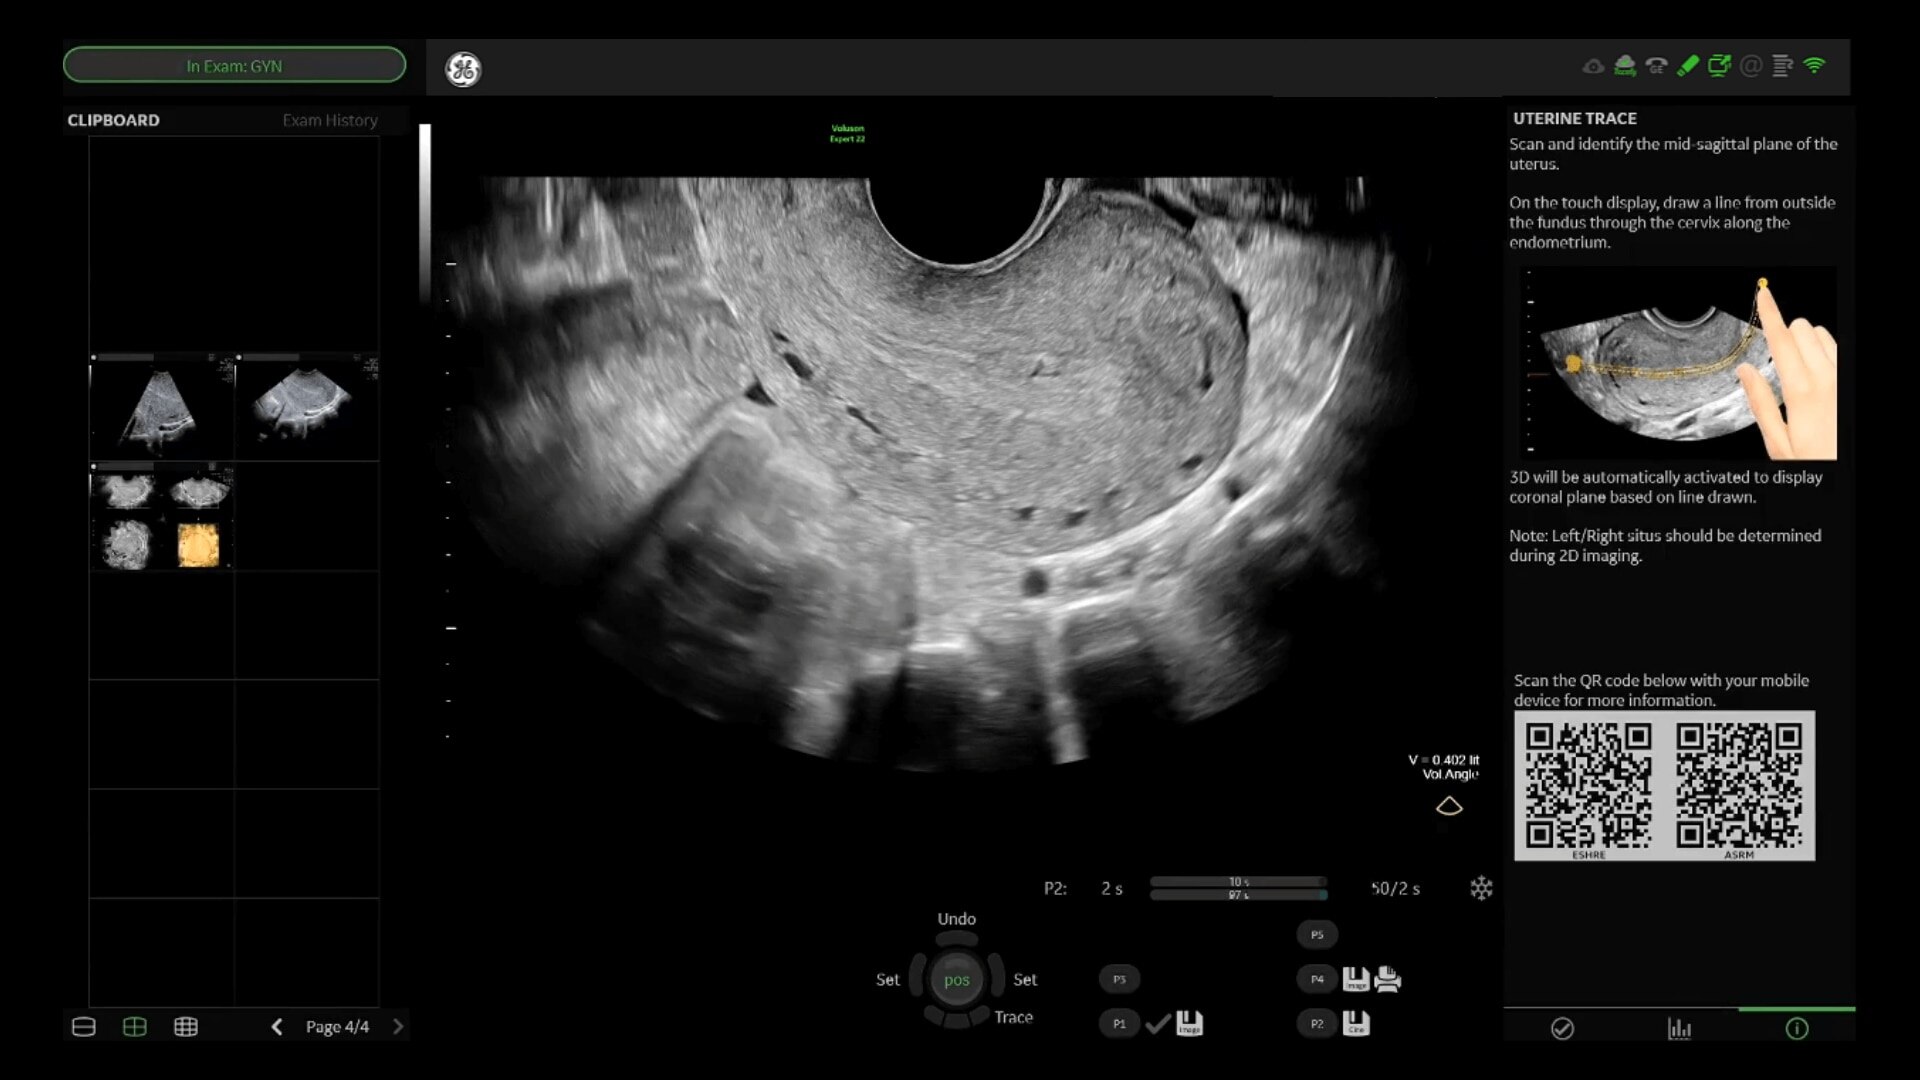

Uterine Trace

Easy display coronal view of uterus.

• Uterine Trace acquires the volume & then displays the coronal view of the uterus to simplify identification & reporting of uterine malformations.

• Easy, accessible 3D for simple, efficient gynecology exams

• Adding 3D can provide more information to help inform your diagnosis and treatment plan. With a comprehensive set of 3D tools, you’ll have everything you need to easily obtain views not possible with standard 2D views.

• Uterine Trace acquires the volume and then displays the coronal view of the uterus linking to ASRM, ESHRE and ESGE Uterine Classification guidelines to simplify identification and reporting of uterine malformations